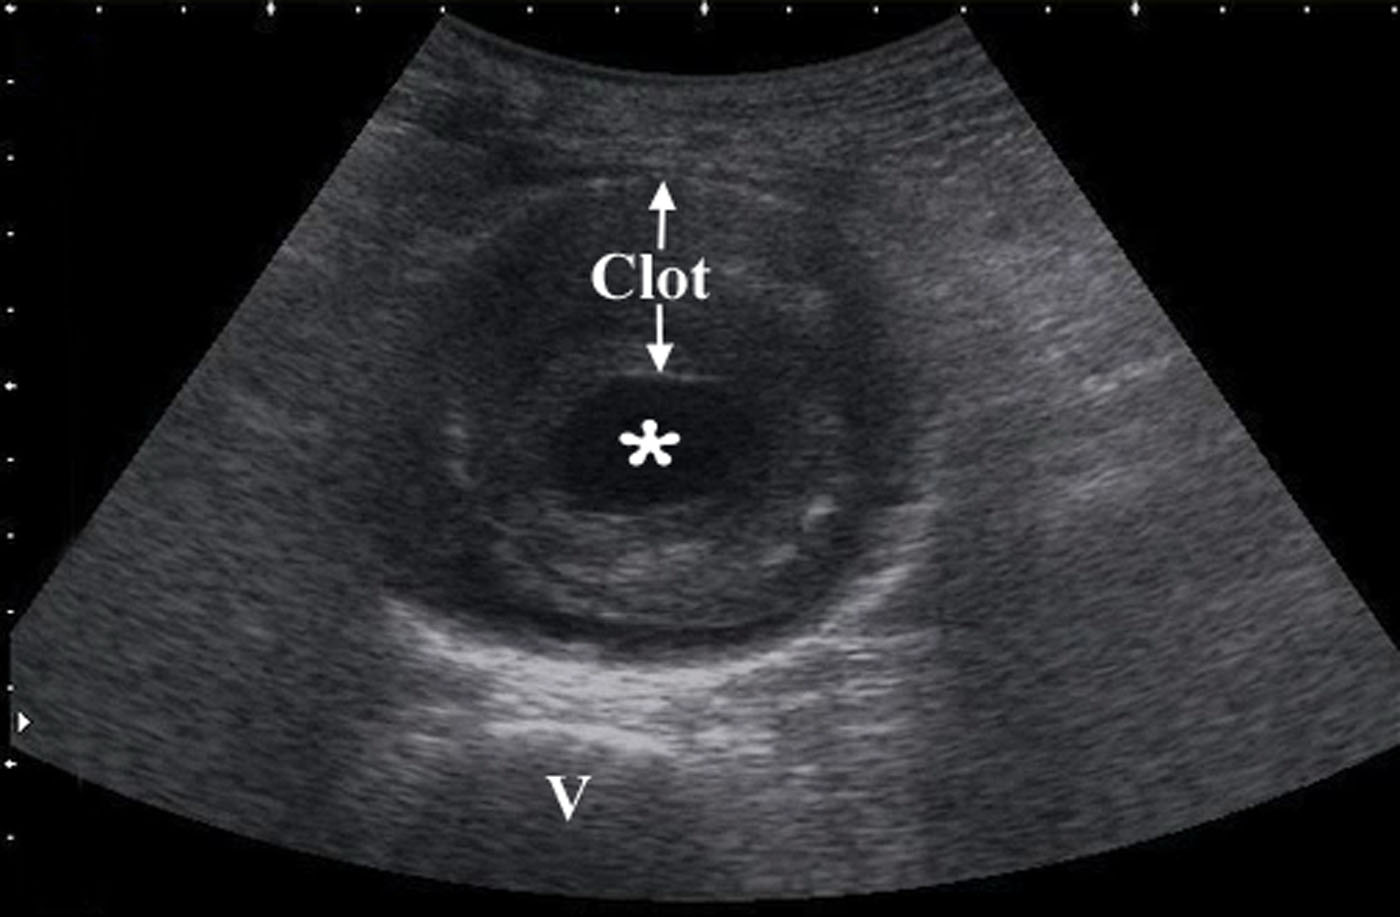

- Obtain measurements of aorta from outer wall to outer wall. Since aneurysms will often contain a thrombus, and with time this becomes calcified and hyperechoic, one may accidentally mistake the inner rim of the thrombus for the aortic wall. Doing this will lead a falsely decreased measurement of the true aortic diameter, possible causing the aneurysm to be missed completely.

- Figure 9. Transverse view of a 7 cm AAA with intraluminal clot (* on the lumen, “v” denotes vertebral body)